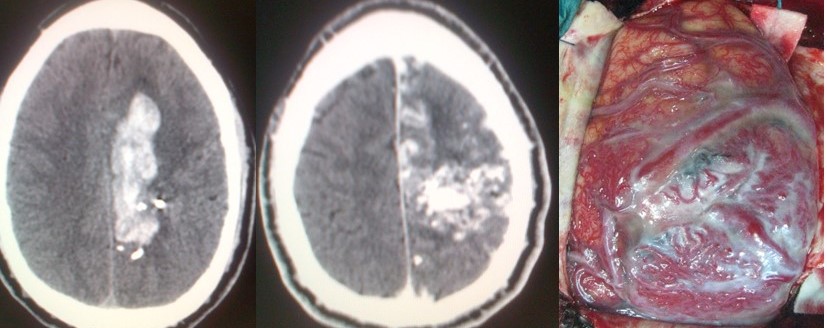

- Accidente cerebrovascular hemorrágico ó hemorragia cerebral espontánea: En él la hemorragia tiene lugar en el interior del parénquima cerebral. Su causa más frecuente es la hipertensión. En otros casos puede deberse al debilitamiento de los vasos sanguíneos debido a la «angiopatía amiloide», típica de personas mayores de 70 años. Facilitada por los tratamientos anticoagulantes, puede también estar provocada por las lesiones previamente descritas (aneurismas, MAVs, tumores cerebrales, etc). Se trata de un cuadro grave que se manifiesta del mismo modo que un ictus. Ha de considerase la evacuación quirúrgica en caso de que la hemorragia alcance un volumen crítico, se acompañe de un deterioro del nivel de conciencia y se localice en un punto accesible.

- Infarto cerebral maligno: Es un infarto cerebral de grandes dimensiones en el que la inflamación que tiene lugar en el parénquima afectado ejerce un efecto compresivo sobre el resto del cerebro, lo que puede conducir al coma y al fallecimiento en más de un 80% de los casos si no se pone remedio. El remedio en este caso viene dado por la craniectomía descompresiva que ha demostrado reducir de manera importante la mortalidad y en menor medida las secuelas neurológicas.